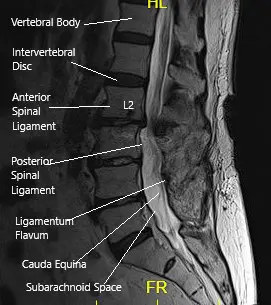

MRI of the LS spine in sagittal section

MRI of the LS spine in sagittal section.

CT scan signs of early screw loosening are seen. However, signs of bony ankylosis from L3-5 are also present. Degenerative spinal stenosis at L2-3 was present and was relatively unchanged since the most recent prior exam in 2018 but demonstrates progressive stenosis over the sequence of scans. MRI showed adjacent segment disease at L2-3 and L5-S1 with nerve root compressions.